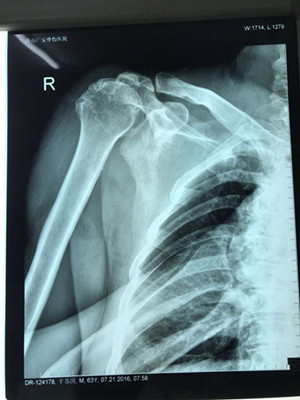

據(jù)了解,干大伯半年前因外傷導(dǎo)致頸椎外傷伴截癱,右肩關(guān)節(jié)脫位伴巨大肩袖斷裂,曾在廣安醫(yī)院接受頸椎手術(shù),術(shù)后恢復(fù)良好。后來,干大伯要求進(jìn)一步對肩關(guān)節(jié)進(jìn)行治療。廣安醫(yī)院副院長危立軍及運(yùn)動(dòng)醫(yī)學(xué)科主任羅軍對其進(jìn)行詳細(xì)檢查后,認(rèn)為干大伯的右肩存在巨大不可修復(fù)肩袖撕裂伴嚴(yán)重的關(guān)節(jié)炎,肩袖的脂肪浸潤達(dá)到四級,治療上有一定的挑戰(zhàn)性,只能通過特殊類型的人工肩關(guān)節(jié)——反式全肩人工關(guān)節(jié)來重建關(guān)節(jié)功能。

經(jīng)過前期準(zhǔn)備,危立軍副院長及羅軍主任帶領(lǐng)手術(shù)專家團(tuán)隊(duì)為干大伯實(shí)施反式人工肩關(guān)節(jié)置換術(shù)。經(jīng)過一個(gè)多小時(shí)的手術(shù)時(shí)間,干大伯被推出了手術(shù)室。手術(shù)非常順利,刀口小,約10厘米,術(shù)后恢復(fù)快。第二天查房時(shí),干大伯便能佩戴特制的肩肘墊起床活動(dòng),肩關(guān)節(jié)劇痛也大大緩解。